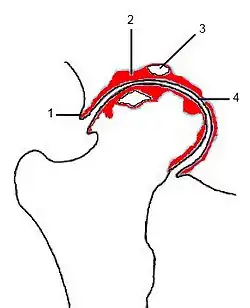

Durch die oben aufgeführten Aufnahmemethoden sind in der Regel alle radiologischen Zeichen der Coxarthrose darstellbar.[7][16] Diese sind:

- Gelenkspaltverschmälerung: anfänglich im Hauptbelastungsbereich, breitet sich in der Folge über den gesamten Gelenkspalt aus

- Geröllzysten: werden besonders kranial der Hüftpfanne groß und verursachen die Inkongruenz der Gelenkfläche

- subchondrale Sklerosierung: besonders die Hüftpfanne ist betroffen

- Osteophyten: besonders lateral-kranial und medial-kaudal an der Hüftpfanne (Azetabulum); seltener am Oberschenkelknochenkopf („capital drop“)

Radiologische Stadieneinteilung

(1) (Rand-)Osteophyt

(2) subchondrale Sklerosierung

(3) Geröllzyste

(4) Gelenkspaltverschmälerung

Für die radiologische Stadieneinteilung wird die Klassifikation nach Kellgren und Lawrence („K & L“-Score; 1963) empfohlen, die die Arthrose in vier Stadien einteilt:[19]